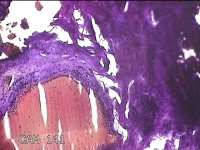

右拇指肿块

性别

女

年龄

73岁

临床诊断

右拇指肿物性质待查

一般病史

标本名称

大体所见

灰白粉红色肿物2.2x1.3x0.3cm一个,表面糜烂,切面灰白粉红色,质软。